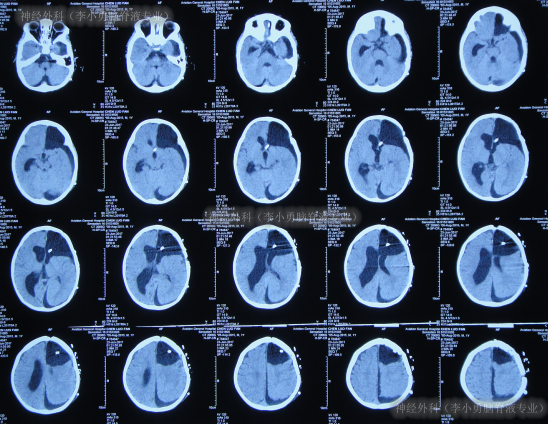

2017年7月20日(癫痫灶切除术后86天即脑室腹腔分流管脑室端探查术后3天,又即脑室腹腔分流术后30天),入院时:高热39.2度,时常哭闹,头围大至55厘米(1岁婴儿头围正常范围为42.6cm-50.5cm),理解力低于同龄人。左侧额颞顶可见一弧形手术切口疤痕,切口缝线仍未拆除;左额可见一长约3cm纵行手术切口疤痕,愈合不良,相应头皮水肿明显;左侧前胸壁引流管走行区可见皮肤隆起;腹部稍膨隆(图-15)。

图-15:2017年7月20日入院时

入院时头颅CT示癫痫术后,左侧额顶骨术后改变,左侧侧脑室引流术后状态,幕上脑室系统扩,多处硬膜下积液、部分见积气(图-16)。

图-16:2017年7月20日头颅CT

入院当天拔除了原脑室腹腔分流管+侧脑室外引流术。术后次日引流出黄色的脑脊液(图-17)。

图-17:2017年7月21日

入院5天即2017年7月24日,体温由入院时连续高热39.2度降至37.2度,情绪变稳定(图-18);原分流管脑室端细菌回报为表皮葡萄球菌。

图-18:2017年7月24日

入院7天即2017年7月26日,体温变得正常,查头颅CT示脑室外引流术后状态(图-19)。

图-19:2017年7月26日头颅CT

入院12天即2017年7月31日,进行了右侧侧脑室腹部外引流术,术前术后头颅CT对比(图-20)。

图-20:2017年7月31日术前术后头颅CT

继续治疗1月的时间,期间患儿身体状态变得越来越好,情绪愉悦,肢体活动正常,期间2次查头颅CT均示脑室进一步缩小(图-21)。

图-21:2017年8月3日

2017年10月8日(李小勇脑脊液专业治80天)出院,出院时:精神状态好,肢体活动正常,能自己走路稍不稳,可简单言语交流;头围由入院时55cm缩小至51.5cm(图-22);出院时头颅CT示脑室分流术后状态,无异常(图-23)。

图-22:2017年10月8日

图-23:2017年10月8日头颅CT